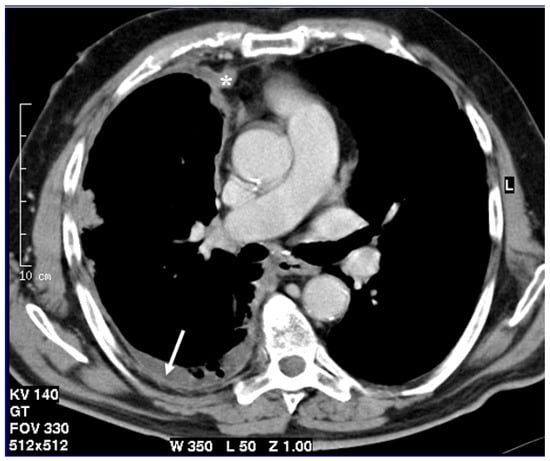

Figure 3.

T2-weighted image acquired in the axial plane clearly demonstrates circumferential pleural thickening with mediastinal pleura involvement (asterisk) and pleural effusion (arrow).